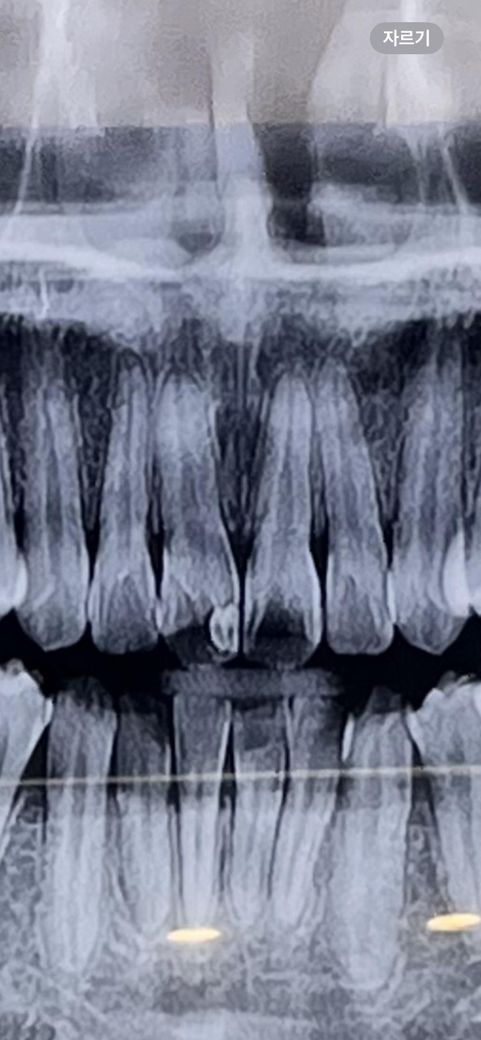

앞니 충치인 것 같나요? 빠른 답변 부탁드립니다 ㅠㅠ

병원에서는 아무 말도 없으셨는데, 잇몸 통증인지 자꾸 무겁고 우리하게 아프고 불안해서 질문합니다

앞니 레진은 충치 치료 아니고 미용목적이었습니다

• 1번 째 사진

사진으로 봤을 때 레진 충전 부위 주변으로 방사선 음영이 보입니다.

이런 경우에는 레진을 따라서 충치가 생겼을 가능성이 있어요.

정확한 확인을 위해서는 직접 눈으로 확인을 하는 것이 좋습니다 자세한 확인을 위해서 치과에서 진료를 받아 보세요.